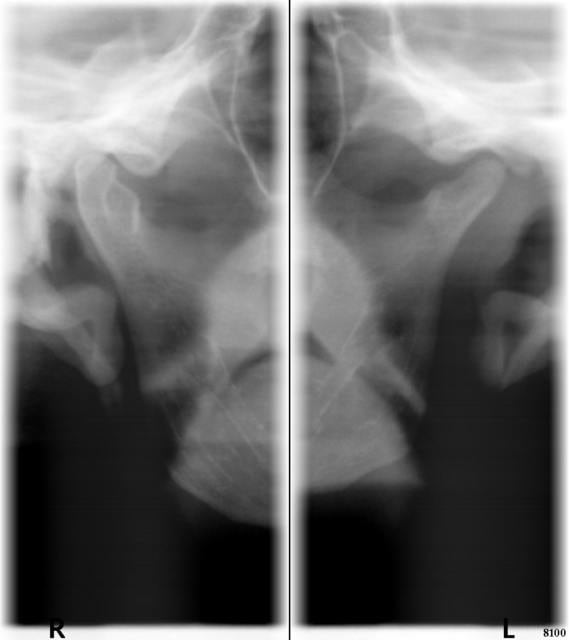

J'ai réalisé un cliché des ATM ce matin pour vous le soumettre.

Comme elle déménage ce week-end, je n'aurai plus le plaisir de tenter de nouvelles solutions. Mais je reste un peu chiffon avec cette histoire d'ATM... Je note bien une certaine asymétrie sur le cliché radio, mais j'avoue que j'ai encore pas mal de lacunes à combler en occluso, et particulièrement en lecture de radio d'ATM.